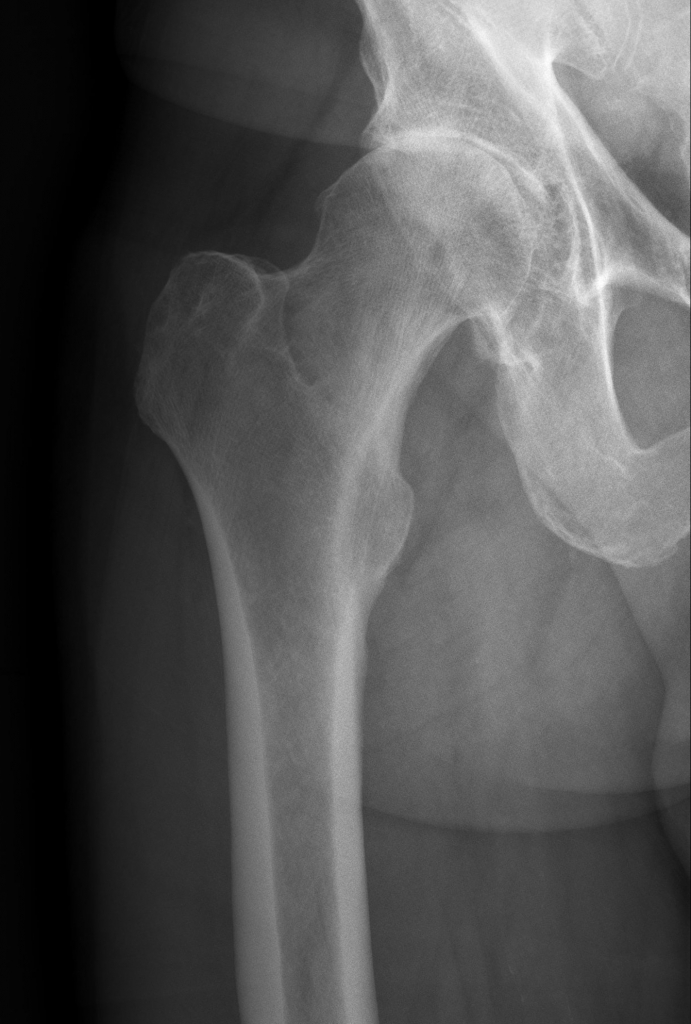

DAS SCHMERZHAFTE HÜFTGELENK:

Die Abnützung des Hüftgelenkes (Arthrose) führt zu immer wieder kehrenden Schmerzen im Bereich des Hüftgelenkes, vor allem im Bereich der Leiste. Durch den Verlust des Knorpels kommt es zur Gelenksentzündung und zu organischen Veränderungen im Gelenk. Als Abwehrmaßnahme des Körpers wird nun durch Knochenanbau versucht, die Bewegung des Gelenkes einzuschränken und dadurch die Entzündungen zu minimieren. Dadurch kommt es allerdings auch zu einer mechanischen Einengung im Gelenk, damit zur Bewegungseinschränkung im Hüftgelenk und wiederum zu Schmerzen.

Dieser Teufelskreis kann nur schwer durchbrochen werden. Die anfangs leichten Schmerzen kommen im Intervall immer häufiger vor und werden stärker. Die Gelenkskapsel kontrahiert sich weiter und die Muskulatur verkürzt sich, die Schmerzen können nun von der Leiste weiter in den vorderen Oberschenkel wandern und rund um das ganze Gelenk auftreten. Nun ist der ideale Zeitpunkt gekommen, um einen Gelenkersatz durchführen zu lassen.